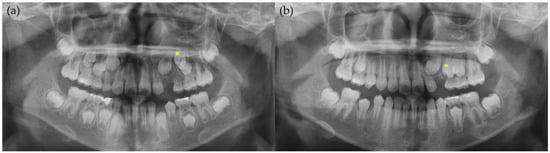

2. Case Report